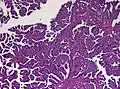

Plexuspapillom Detail Plexuspapillom Overview

Plexuspapillom Overview